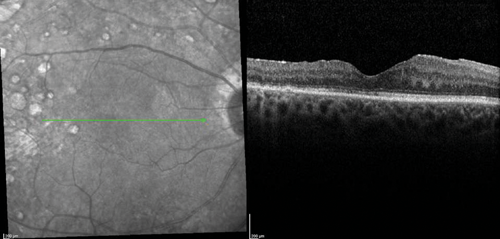

The clinical efficacy and safety of the drug have been also reported in two case reports of vitrectomised eyes with persistent DMO with both cases showing a desirable anatomical outcome. In one case, the authors have suggested that vitrectomy seemed to have enhanced the performance of the implant in-situ and achieved complete DMO resolution [19]. In a recently presented series of 20 post PPV eyes of 18 patients treated with Iluvien, a mean change of BCVA of +9 ETDRS letters (range -6 to +27) as well as mean reduction of CRT by -224µm (-595 to +126) were reported after a mean follow-up period of 201 days (range: 45 to 367 days) (SFO Paris 2016). Further real-life data of Iluvien in vitrectomised eyes with comparable clinical outcomes are awaited with interest. The author’s experience with the drug so far is in-keeping with published cases (Figure 1).

Figure 1 (d).

Figure 1 (e).

Figure 1: Case study for management of post-vitrectomy refractory DMO: (a) Pre-vitrectomy; (b) Post-vitrectomy; (c) Post six intravitreal anti-VEGF treatment with sub-optimal response; (d) Post-Iluvien one month. Complete resolution of DMO; (e) Post-Iluvien 10 months. Maintained response to treatment. (Courtesy of Mr David H W Steel - Sunderland Eye Infirmary).